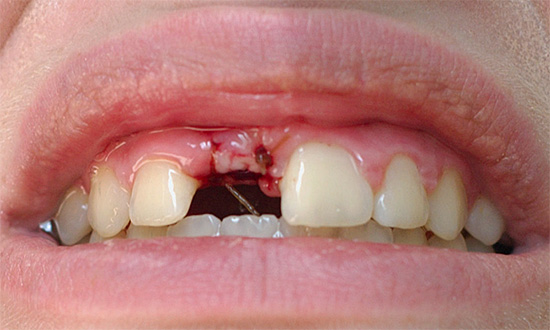

A foto abaixo mostra como o buraco fica logo após a remoção do dente do siso, anteriormente escondido sob a gengiva:

O coágulo sanguíneo que se formou após a extração do dente muda em alguns dias, da Borgonha para a mais clara, com um tom amarelado. A cor, neste caso, é determinada por processos fisiológicos naturais: o componente vermelho dos glóbulos vermelhos (hemoglobina) é gradualmente lavado pelo fluido da cavidade oral, mas o chamado esqueleto de fibrina é preservado, que serve como base estrutural do trombo, o que evita o sangramento do orifício do dente extraído.